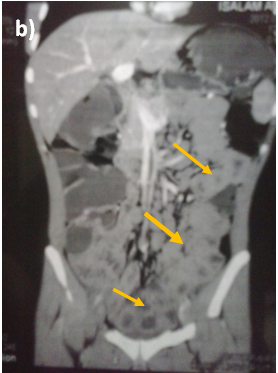

Abdominal ultrasound showed uniform circumferential mural thickening of the small bowel loops, so we proceeded to C.T Enterography. As shown in Figure 1, there is diffuse uniform thickening of the small bowel loops mainly involving the ileum with no focal thickening or masses. Then upper endoscopy and colonoscopy were performed to the patient and they showed multiple tiny rounded nodules at the terminal ileum that were biopsied and revealed non-specific inflammation free of granuloma or malignancy. Then we proceeded to double balloon enteroscopy which was done by an over tube double balloon Fuji series endoscopy, which proceeded to about 200cm from the duodenal bulb. Double balloon endoscopy as shown in Figure 2, showed numerous visible mucosal nodules measuring few millimeters in diameter involving the whole part of the small intestine examined which were biopsied. Histopathology revealed chronic inflammatory enteritis with foci of lymphoid aggregates with no atypia or malignancy (Table 1).

Figure 1 C.T. Enterography of the patient that showed diffuse uniform thickening of the small bowel loops mainly involving the ileum with no focal thickening or masses.